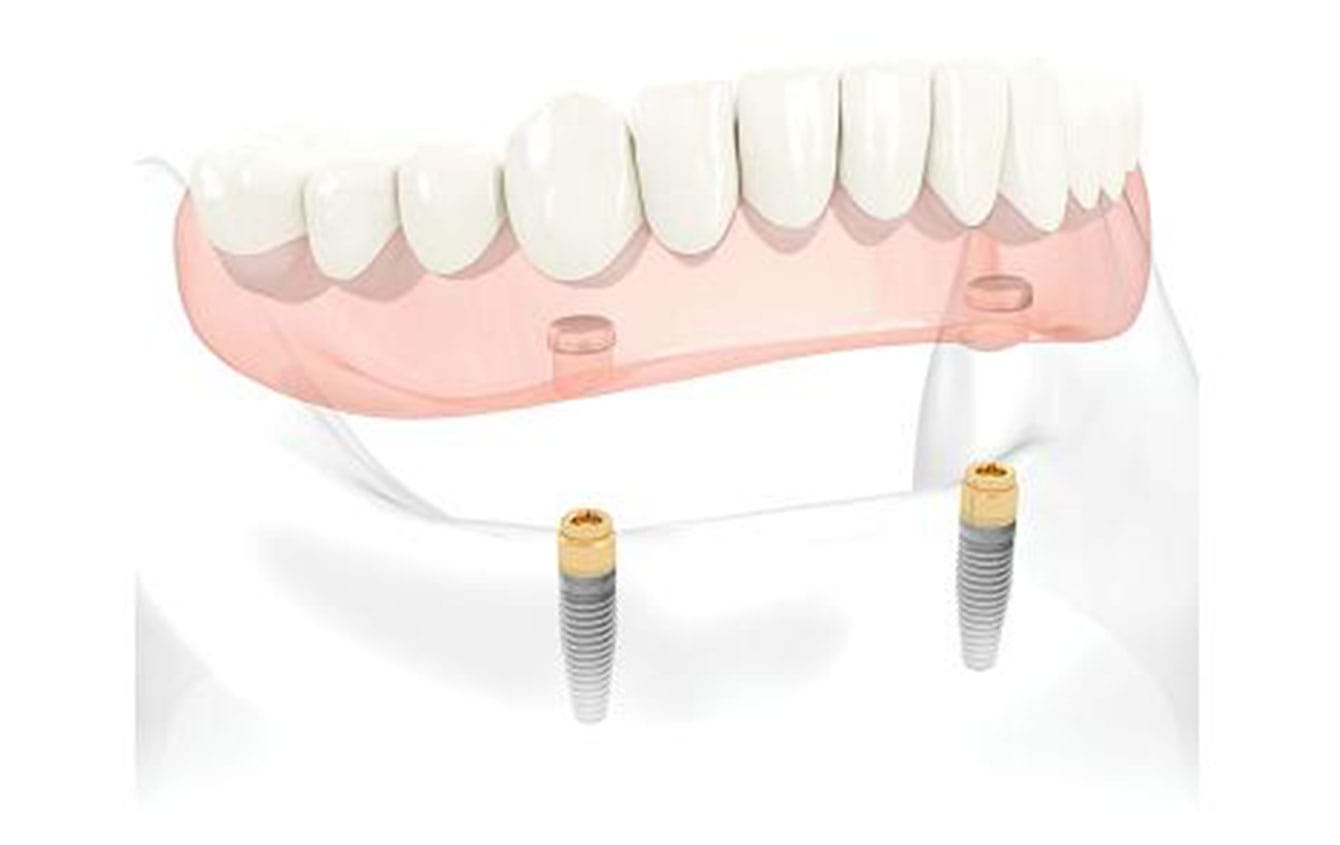

La prothèse amovible complète mandibulaire supra-implantaire sur attachements (Pilier Locator)

Il s’agit d’une prothèse complète muco-portée traditionnelle comportant en plus deux attachements supra-implantaires qui permettent d’améliorer de façon significative la rétention et la stabilisation de la prothèse.

Elle est particulièrement appréciée par les patients porteurs de prothèse complète mandibulaire et qui souffrent d’une instabilité handicapante de leur prothèse, les obligeant parfois à utiliser des crèmes adhésives.

De plus, cette solution prothétique permet aux patients un entretien aisé de leur appareil et au praticien une maintenance facilitée.

Le pilier locator est constitué par une partie male composé par un attachement axial directement vissé dans l’implant et une partie femelle située dans la prothèse amovible et composée d’un boitier recevant une gaine interchangeable.